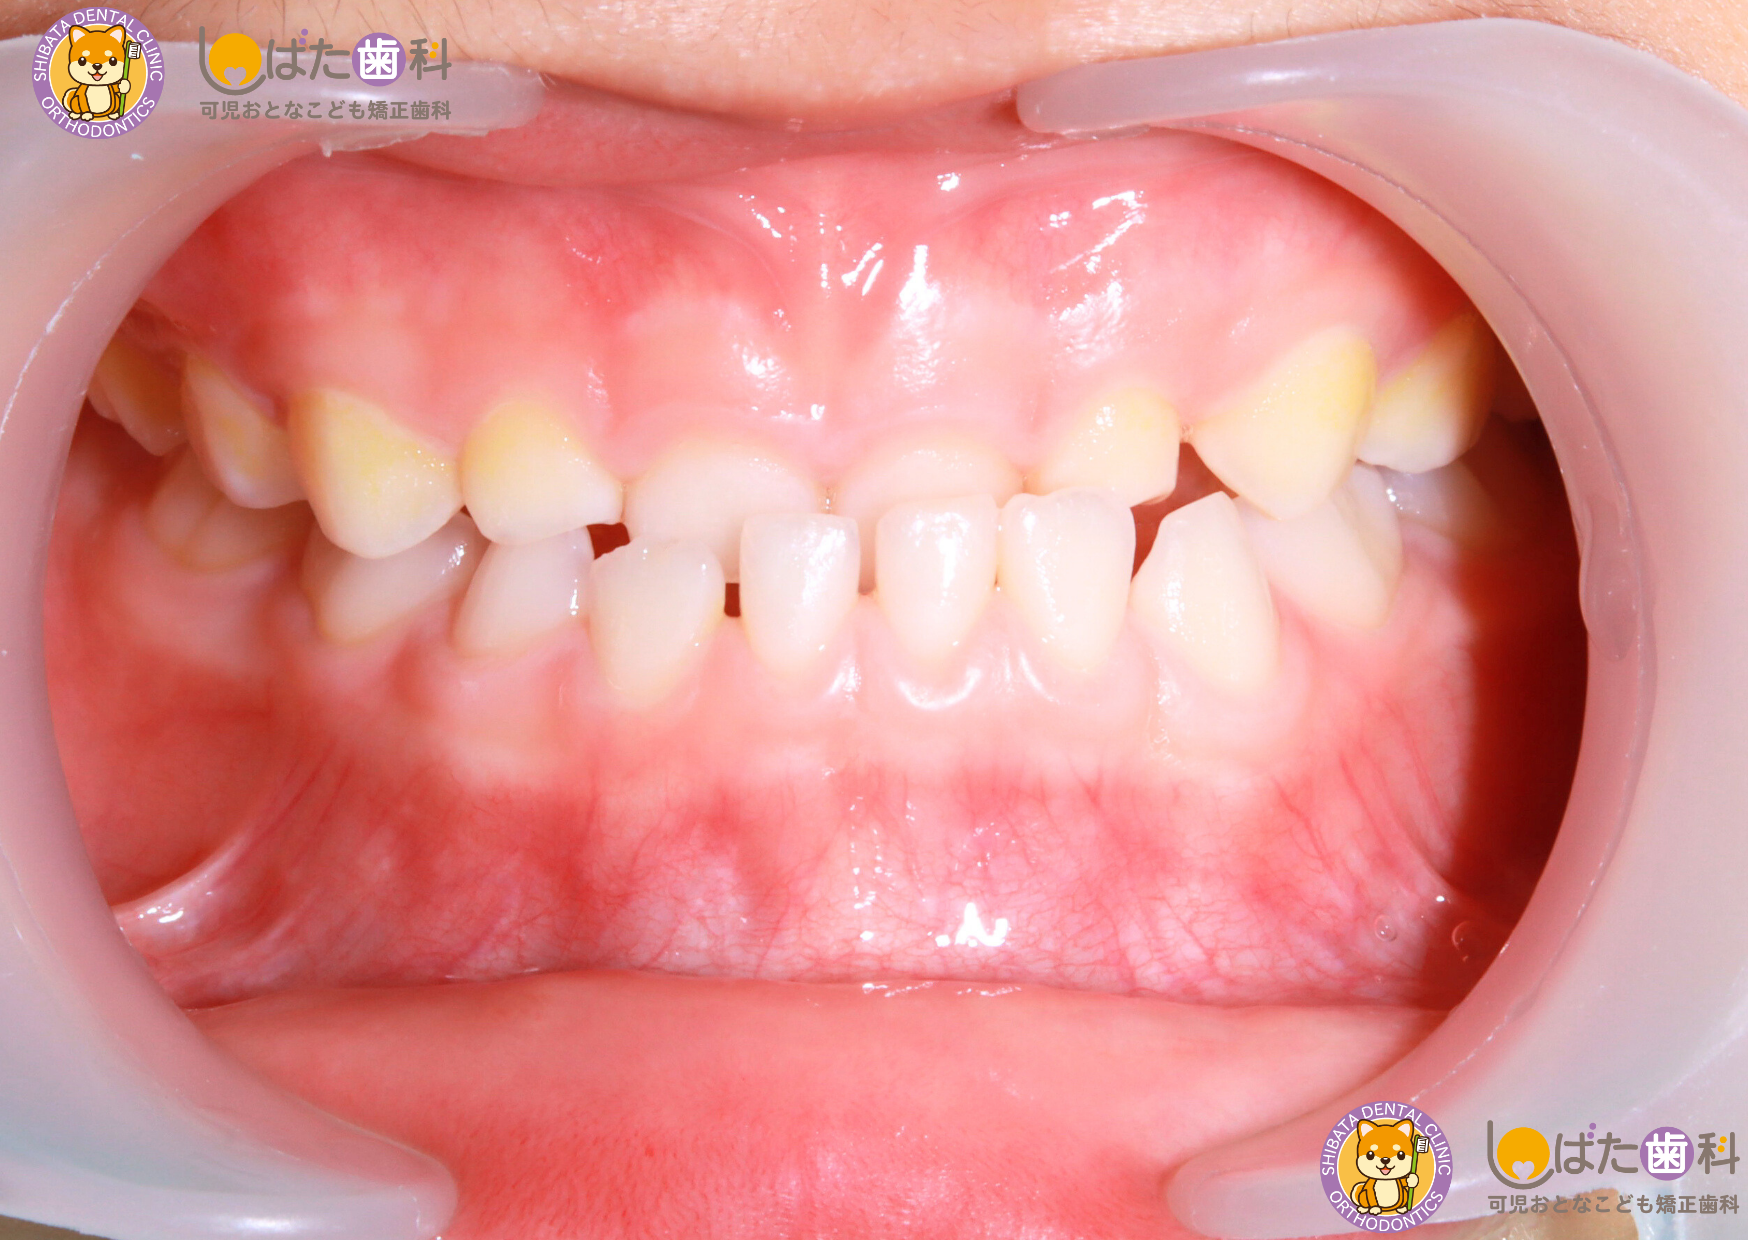

・反対咬合(はんたいこうごう)

通常、上の歯が下の歯に被さるのが正しい噛み合わせですが、下の歯が上の歯より前に出てしまっている状態を「反対咬合」といいます。反対咬合は**受け口(うけぐち)**とも呼ばれ、食事の際の噛みづらさや、発音への影響が出ることがあります。

また、反対咬合が進行すると、顎の成長バランスが崩れたり、顔貌に影響を及ぼす可能性があります。そのため、特に成長期のお子さまの場合は、早期の治療が推奨されることがあります。